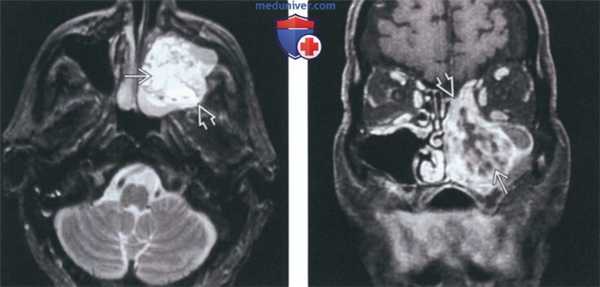

(Слева) На аксиальной МРТ (Т2 ВИ FS) определяется амелобластома верхней челюсти с солидным и кистозным компонента ми, выглядящая многокамерной. Обратите внимание на типичный гиперинтенсивный Т2 сигнал в кистозных компонентах и вздутие задней стенки верхнечелюстной пазухи.

(Справа) На корональной MPT (Т1 ВИ C+ FS) у этого же пациента определяется контрастное усиление перегородок, обычно наблюдающееся при амелобластоме. Местно агрессивную природу этой опухоли доказывает ее распространение в полость носа и ячейки решетчатого лабиринта.